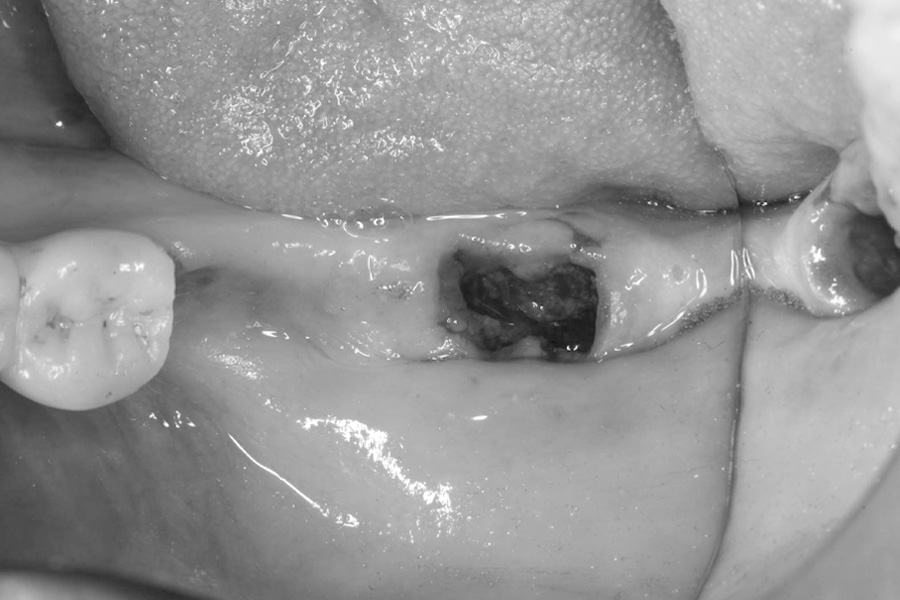

治療前

治療前症例写真

抜歯直後

抜歯直後症例写真

ブリッジの土台にしていた歯の保存ができなくなり、再治療を行いました。

右下3番、7番の抜歯後、右下3番、5番、6番相当部分にインプラントを3本埋入し、補綴を行いました。